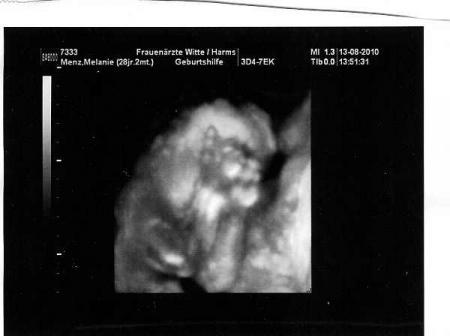

Und noch eins...

Bild zu